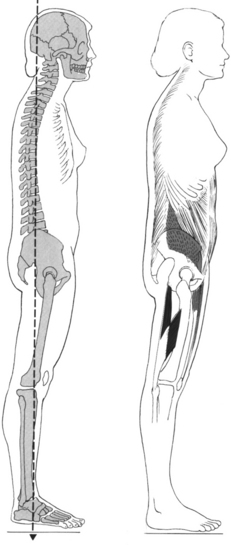

This text discusses musculoskeletal pain syndromes arising from tissue alterations that are caused by movement. Movement is considered a system that is made up of several elements, each of which has a relatively unique basic function necessary for the production and regulation of movement. Various anatomic and physiologic systems are components of these basic elements (Figure 2-1). To understand how movement induces pain syndromes, the optimal actions and interactions of the multiple anatomic and physiologic systems involved in motion must be considered. The optimal function and interaction of the elements and their components are depicted in the following kinesiologic model.

The elements of the model are (1) base, (2) modulator, (3) biomechanical, and (4) support. The components that form the base element, the foundation on which movement is based, are the muscular and skeletal systems. The components of the modulator element regulate movement by controlling the patterns and characteristics of muscle activation. The modulator element of motion is the nervous system, because of its regulatory functions (described in the sciences of neurophysiology, neuropsychology, and physiologic psychology). Components of the biomechanical element are statics and dynamics. Components of the support element include the cardiac, pulmonary, and metabolic systems. These systems play an indirect role because they do not produce motion of the segments but provide the substrates and metabolic support required to maintain the viability of the other systems.

Pathokinesiology is described by Hislop as the distinguishing clinical science of physical therapy, and it is defined as the study of anatomy and physiology as they relate to abnormal movement.25 Based in part on word construction and in part on clarification of causative factors, pathokinesiology emphasizes abnormalities of movement as a result of pathologic conditions. The pathokinesiologic model (Figure 2-2) depicts the role of disease or injury as producing changes in the components of movement, which result in abnormalities of movement. In the Nagi model of disablement,45 disease leads to impairments that cause functional limitations with the possible end result of disability. Impairments are defined as any abnormality of the anatomic, physiologic, or psychologic system. Therefore abnormalities of any component system or of any movement are considered impairments.

A common belief is that movement impairments are the result of pathologic abnormalities, but the thesis of this text is that movements performed in daily activities can also cause impairments that eventually lead to pathologic abnormalities. Therefore a different model is proposed to characterize the role of movement in producing impairments and abnormalities. The empirical basis of this model stems from observations that repetitive movements and sustained postures affect musculoskeletal and neural tissue. The cumulative effect of repetitive movements is tissue damage, particularly when the movements deviate from the optimal kinesiologic standard for movement. Human movements involve similar internal and external forces as do mechanical systems.49 In mechanical systems, maintaining precise movement is of such importance that the science of tribology is devoted to the study of factors involved in movement interactions. Tribology is defined as the study of the mechanisms of friction, lubrication, and wear of interacting surfaces that are in relative motion.1 Based on the similarities of biomechanical and mechanical systems, the premise for ensuring the efficiency and longevity of the components of the human movement system is maintaining precise movement of rotating segments. Although the adaptive and reparative properties of biological tissues permit greater leeway in maintaining their integrity than do nonbiologic materials, it is reasonable to assume that maintaining precise movement patterns to minimize abnormal stresses is highly desirable.

Therapists and other clinicians involved in exercise prescription believe that repeated movements can be used therapeutically to produce desired increases in joint flexibility, muscle length, and muscle strength, as well as to train specific patterns of movement. All individuals who participate in exercise accept the fact that repeated movements affect muscle and movement performance. Thus these individuals should also accept the idea that repeated motions of daily activities, as well as those activities of fitness and sports, may also induce undesirable changes in the movement components. Stretching and strengthening exercises performed for shorter than 1 hour are believed to produce changes in muscular and connective tissues. However, repeated movements and sustained postures associated with everyday activities that are performed for many hours each day may eventually induce changes in the components of the movement system. The inevitable result is the development of movement impairments, tissue stress, microtrauma, and eventually macrotrauma. In accordance with this proposed theory, the effects of repeated movements and sustained postures modify the kinesiologic model so that it becomes a kinesiopathologic model (Figure 2-7), that is, a study of disorders of the movement system.